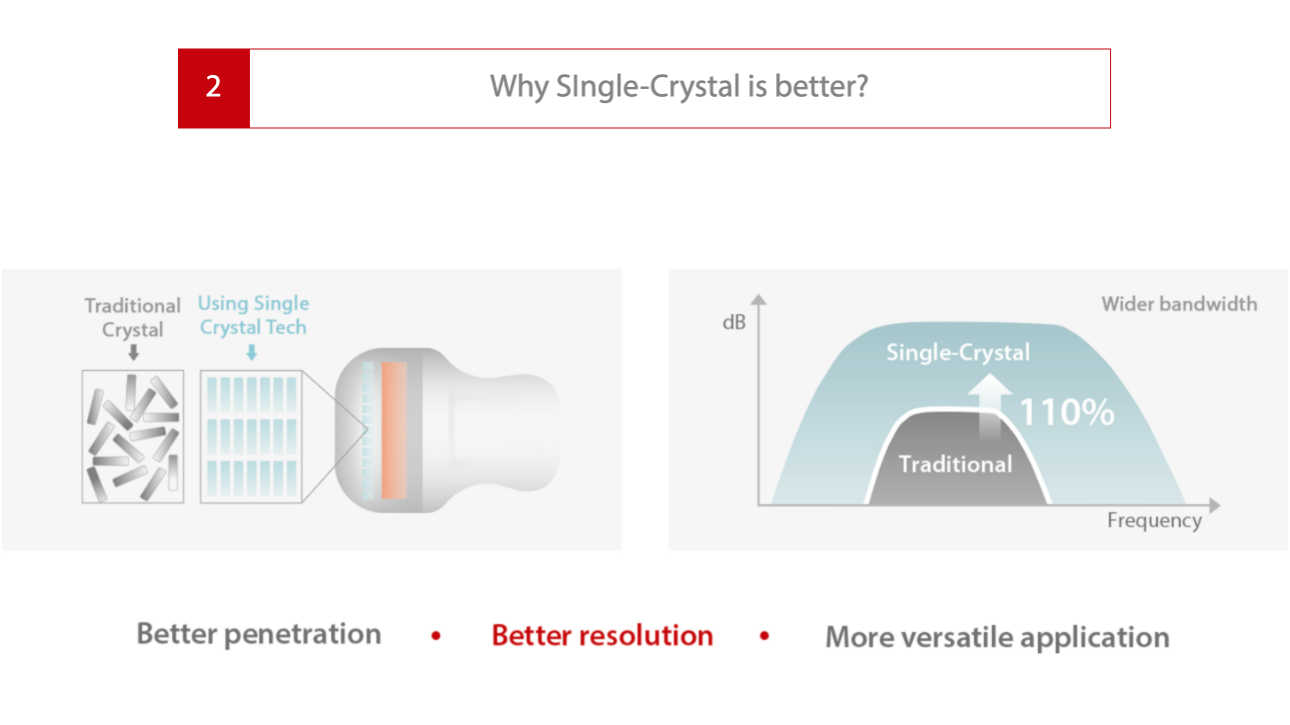

Nivel de cristal Ășnico

2